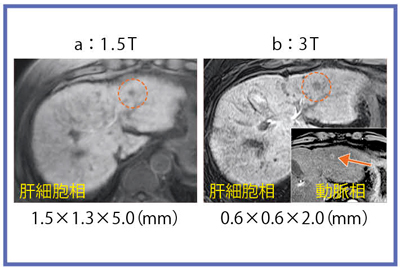

次に,造影能については,T1値を短縮させる緩和試薬(Gd系)の効果が高いことから,高分解能の造影T1強調画像が期待される。図6は,肝細胞がん(HCC)におけるGd-EOB-DTPAの造影能の比較であるが,3Tでは高分解画像でも良好なCNRを保ち,肝硬変での肝実質における不均一性も表現できている。

図6 HCCにおけるGd-EOB-DTPA造影能

3Tでは高分解画像でも良好なCNRを保ち,肝硬変での肝実質における不均一性も表現できている。小さな早期濃染の描出も可能(←)。

図10 HCC症例:Gd-EOB肝細胞相の高分解能画像

3Tでは腫瘍辺縁が明瞭に描出されている。

3Tでは,0.6mm×0.6mm×2.0mmのボクセルサイズで,非常に高分解能の画像を得ることができ(図10),造影画像や,MRCPでも高精細に描出可能である。一方,画像枚数が膨大になるため,ルーチン化にあたって読影時間やPACS容量が問題となり,これらをどのように克服し臨床応用していくかが今後の課題と言える。